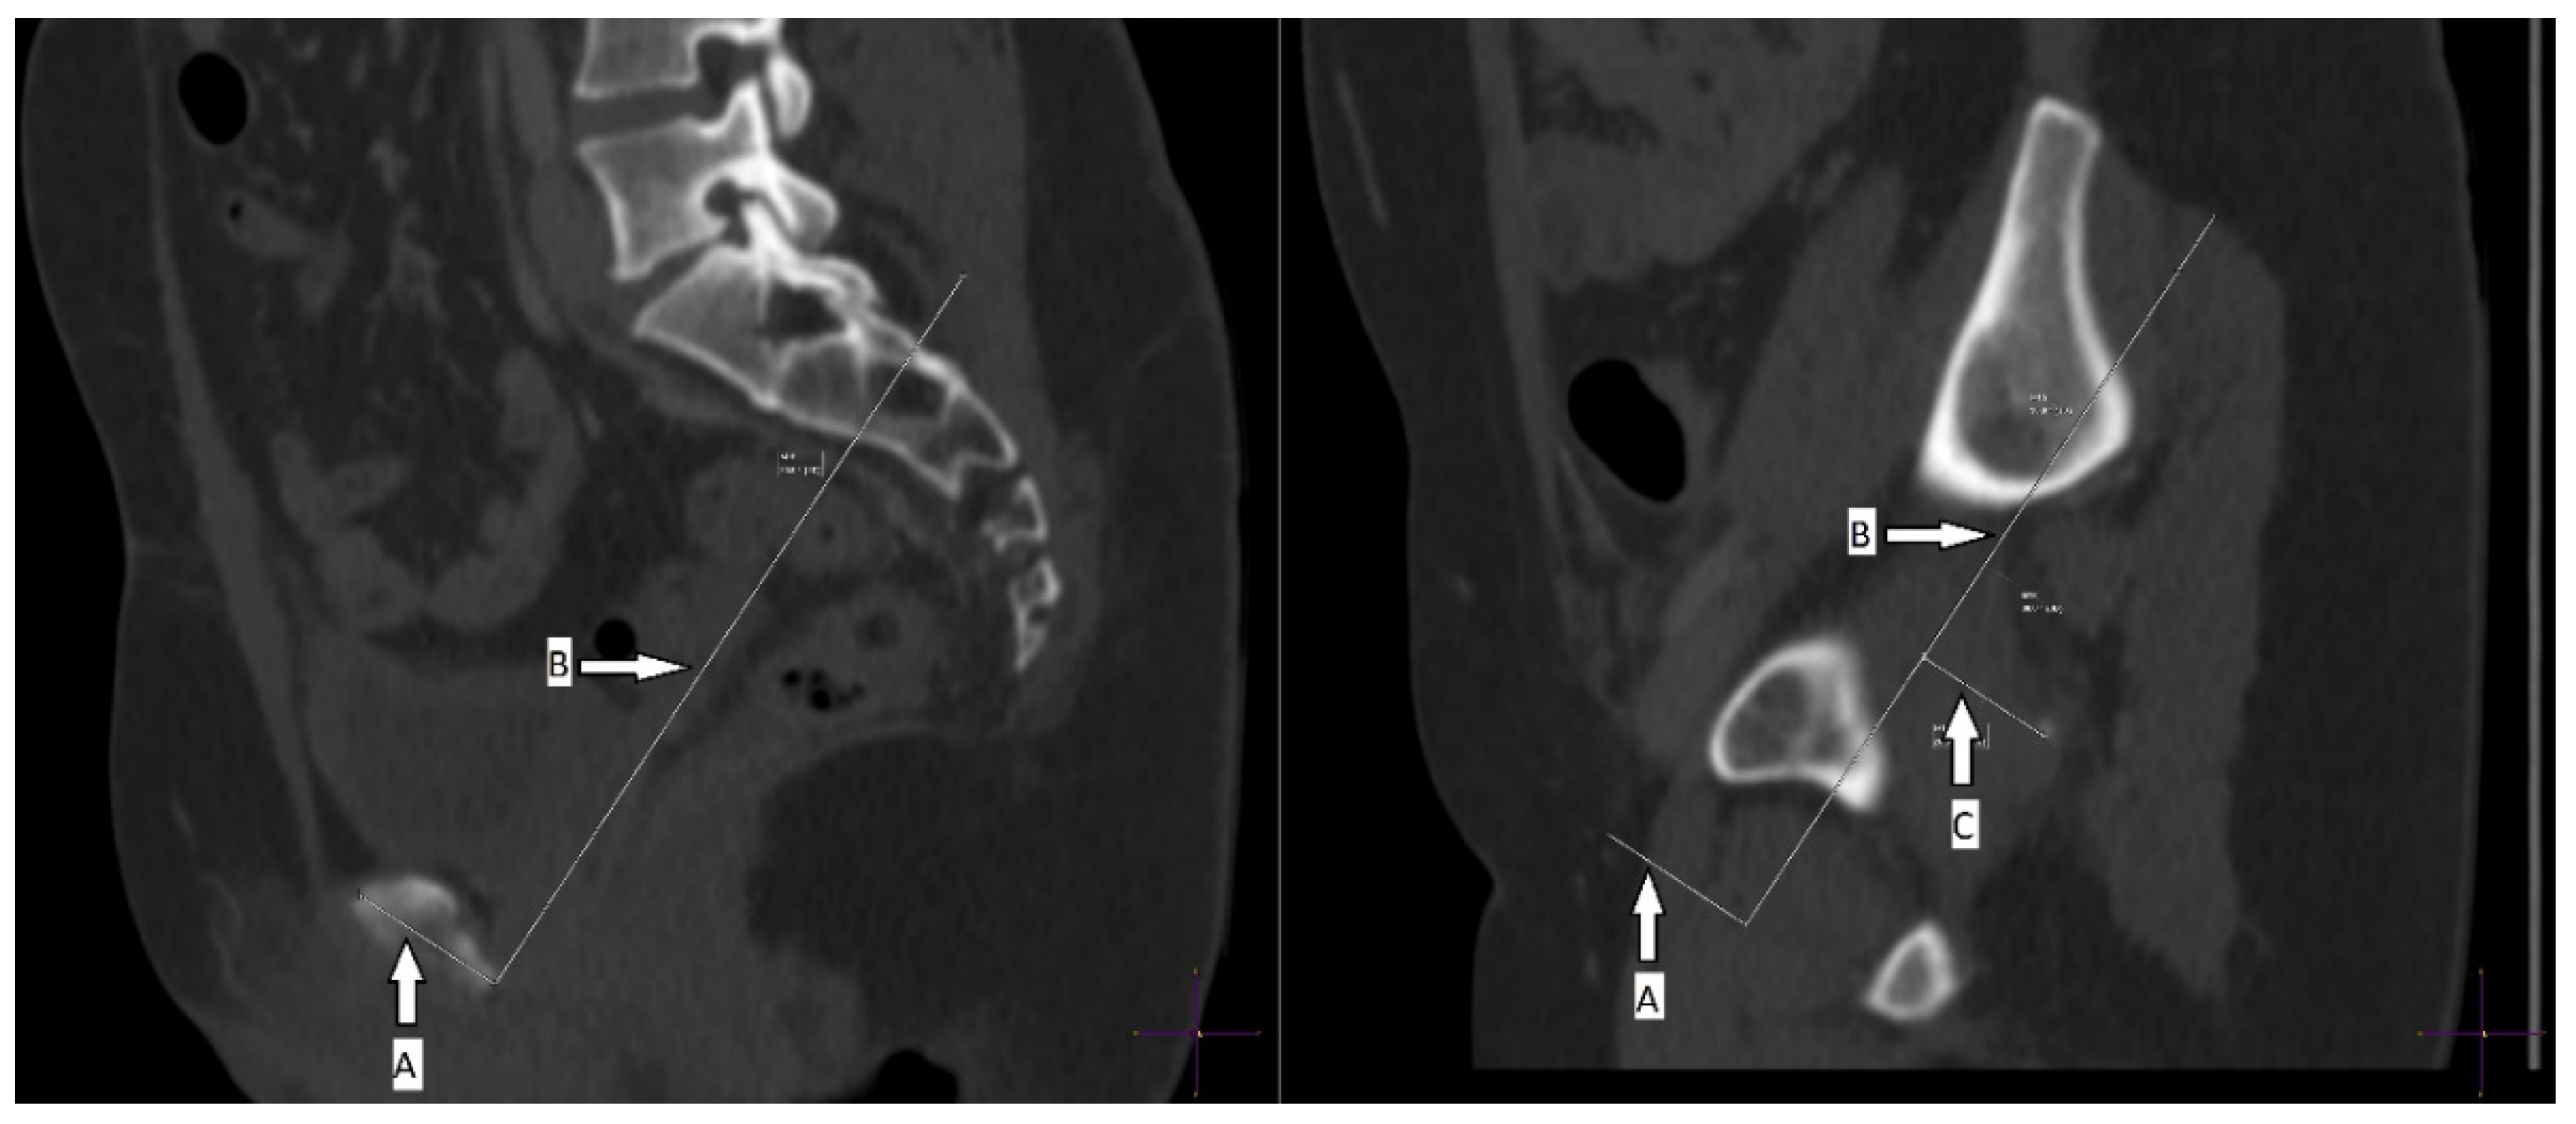

2. Materials and Methods

2.1. CT Measurements